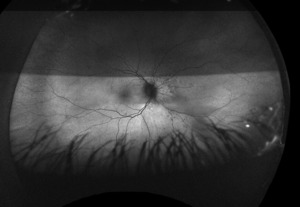

At the follow up, the patient’s vision remained stable without glasses, 20/20-1 OD and 20/25-1 OS. Humphrey Visual Field, Optos, Optos with autoflourescence, repeat B Scan, and color plates were performed at this visit. Color vision was normal in both eyes.

At the end of this visit, a diagnosis of optic nerve head drusen was determined due to the findings on the B-Scan. A highly reflective foci was seen due to the calcification present on the optic nerve head. There was no hyperflourescence seen on the fundus autoflourescent photos, but the drusen were likely buried. A 3-month follow-up was scheduled for repeat dilated fundus exam to ensure hemorrhages were resolving and no changes to the optic nerve head or visual acuity were occurring. The patient was educated on the condition of optic nerve head drusen and its effects on visual fields and vision. He was educated to return to clinic immediately if any changes were noted before the follow-up in 3 months.

After additional testing was completed, and comparison of previous photos were conducted, it was determined that the patient had not only optic disc drusen, but also possible bilateral amiodarone optic neuropathy. The photos 4 months apart shows increasing pallor in the left eye and a blood vessel at 7 o’clock that did not look obscured initially but was evidently more pronounced on the follow up when comparing the initial and follow-up photos. This shows the importance of quality serial fundus photography.

Right image is original exam with inferior hemorrhage. Left image is 4-month follow-up visit. Resolution of the hemorrhage is seen, but atrophy of the disc overall should be noted. Vessel at 7 o’clock should also be noted. It appears much more pronounced than on initial visit.